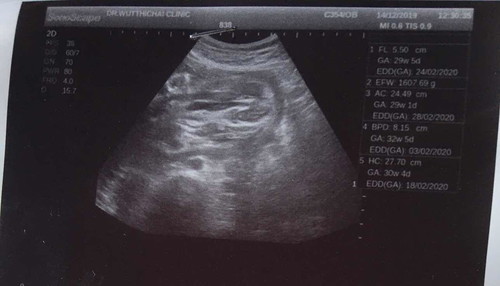

มีใครเคยมีภาพซาวด์แบบนี้แล้วออกมาเป็นผู้ชายบ้างคะ คุณหมอบอกผู้หญิง80% แต่ในภาพน้องกำลังเหยียดขาอยู่ มีโอกาสออกมาเป็นผู้ชายบ้างมั้ย?